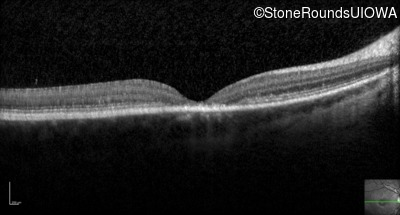

Optical Coherence Tomography - Right - 20/100 -2 sc

Exemplar / OCT Stack